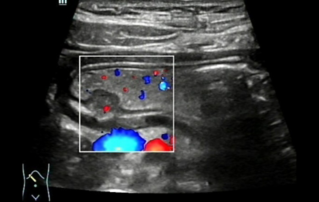

Female pelvic floor anatomy, which developed since the early 20th century, has had a variety of theories, including integral theory, three levels of vaginal support theory, "hammock hypothesis", and three-chamber system. Supporting structures such as pelvic floor muscles, fascia and ligament play an important role in maintaining the normal function of pelvic floor, among which levator ani muscle group is one of the most important supporting structures.